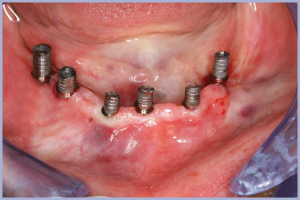

Gli impianti vengono inseriti seguendo le informazioni della scheda allegata compilata dall’odontotecnico (Figg. 54-56).

Al termine di tutti i passaggi la dima viene rimossa, i monconi inconati sui rispettivi impianti, le boccole della protesi avvitate sui monconi e la struttura protesica bloccata alle boccole con composito polimerizzato in situ, per un ideale abbattimento delle discrepanze fra il progetto e la sua realizzazione (Figg. 57-60).

- Figg. 54-56 – Fasi operative della chirurgia guidata

- Fig. 55

- Fig. 56

- Fig. 57 – Situazione a fine intervento